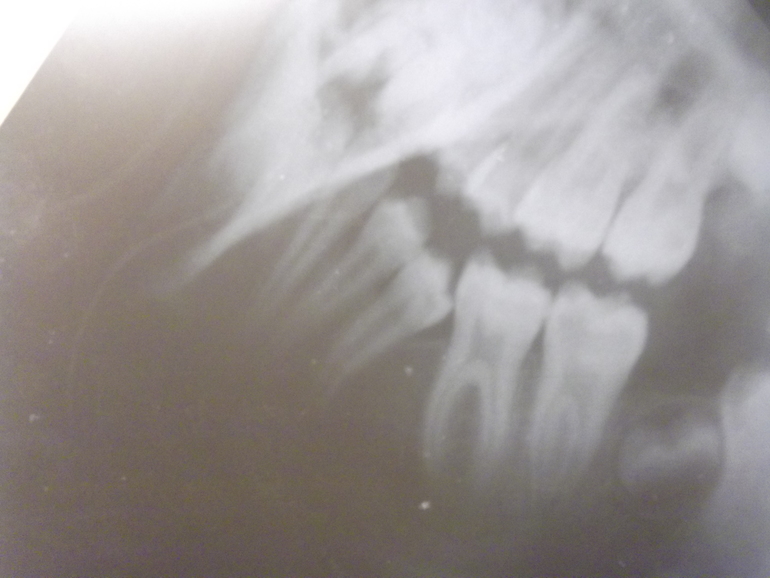

Курочка Опубликовано 6 марта, 2017 Поделиться Опубликовано 6 марта, 2017 (изменено) Ребёнку 11 лет. Зубы молочные поменялись без вмешательств, но 5-ка долго не могла выйти.Осенью 2016 началось , с интервалом через месяц регулярно начало каждого месяца боли/ сводит челюсть, ночами/днями с каждым разом болезненность увеличивается.Челюсть маленькая зубы крупные.И вообще какие у нас перспективы? Изменено 6 марта, 2017 пользователем Курочка Ссылка на комментарий

Yana guapa Опубликовано 13 марта, 2017 Поделиться Опубликовано 13 марта, 2017 Ребёнку 11 лет. Зубы молочные поменялись без вмешательств, но 5-ка долго не могла выйти.Осенью 2016 началось , с интервалом через месяц регулярно начало каждого месяца боли/ сводит челюсть, ночами/днями с каждым разом болезненность увеличивается.Челюсть маленькая зубы крупные.И вообще какие у нас перспективы? фотографии во рту - покажите. Но обычно в таких случаях ортодонт помогает прорезаться зубу правильно и полноценно. Ссылка на комментарий